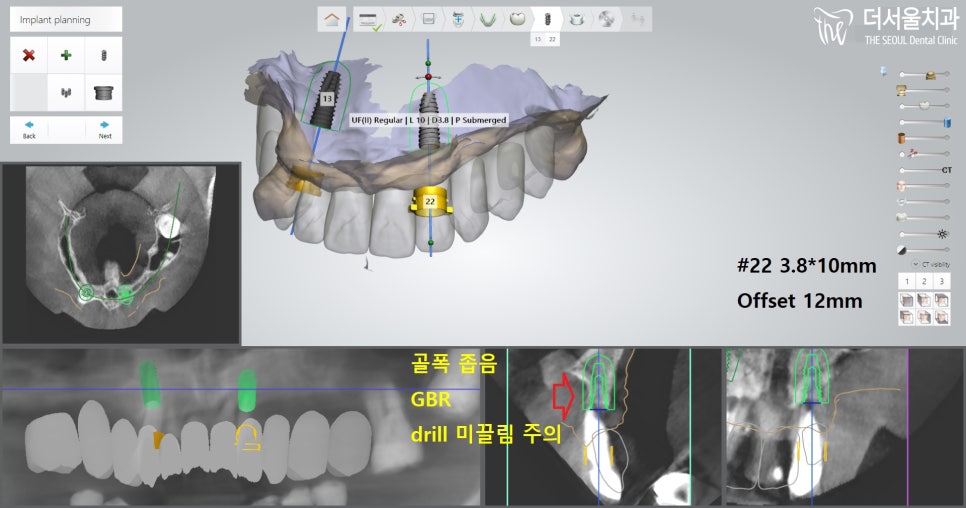

그래서 13번과 22번 위치에 픽스처를 심고,

둘을 지대치로 이용하여

브릿지를 연결시켜 사용하기로 합니다.

아래에 검사를 하는 부분에서

보여지는 것처럼

뼈 상태가 너무 좋지 않기에,

추가적으로 뼈이식을 하기로 합니다.

좀 더 확대해서 보면,

이렇게 픽스처가 골폭을 벗어나있죠?

이러면 제대로 고정되지 않습니다.

결국, 실패로 이어지기에

뼈이식을 해야 되었죠.